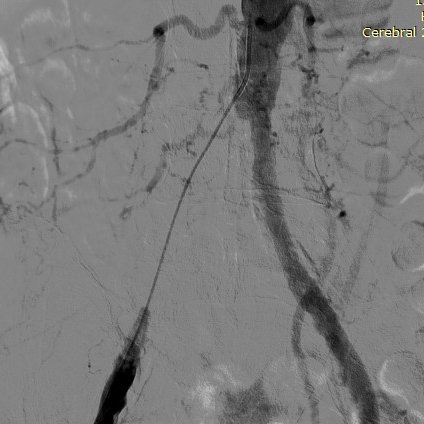

MRI/CT interpretation and Thrombectomy and stenting/ plasty for acute and recurrent stroke. Cerebral DSA

Thrombectomy – mechanical , pharmacological and combined therapy for acute stroke.

Young hypertension, renal ostial stenosis and arterial disease.